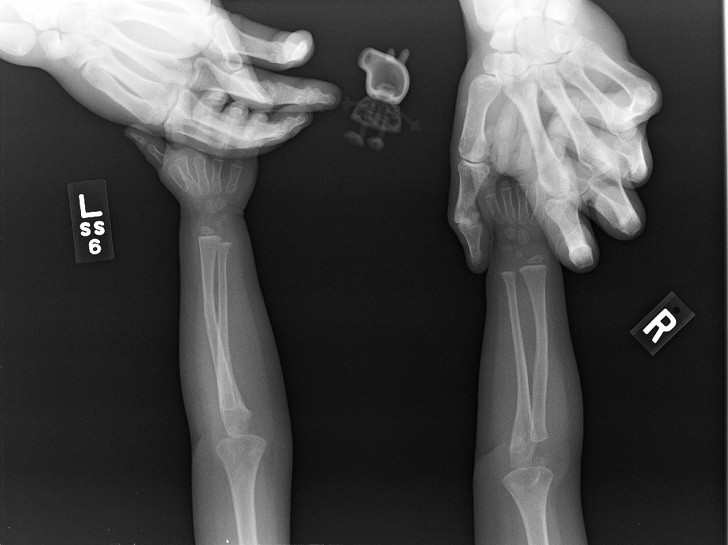

Ljudje smo resnično čudna bitja in se nam lahko zgodijo neverjetno bizarne stvari. Ti rentgenski posnetki bodo šokirali tudi tiste, ki mislijo, da so videli že vse.

Rentgen je eden najboljših izumov človeštva in v nekaterih situacijah je nepogrešljiv. Še posebej zato, ker se velikokrat zgodi, da ljudje, še posebno otroci, požirajo predmete, ki niso del dnevne prehrane. Da ne omenjamo psov, ki poskušajo prežvečiti vse, kar vidijo, in tako velikokrat pogoltnejo neprimerne stvari.

Radiologi so tako že precej navajeni, da na rentgenskih posnetkih vidijo čudne stvari in nekatere izmed teh, ki smo jih za vas zbrali v galeriji, jih sploh niso presenetile. Tukaj je 15+ odštekanih in na trenutke šokantnih rentgenskih posnetkov.